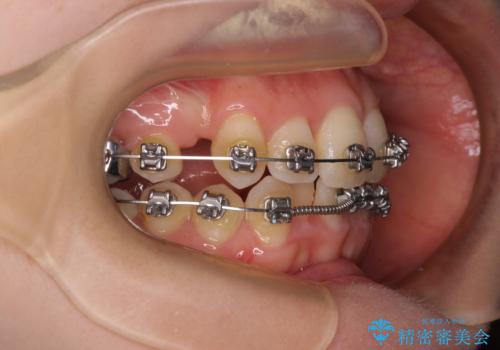

- 矯正装置

- メタルブラケット

- 治療計画

- 八重歯が気になるとのことで来院された患者様です。

上顎前歯部はデコボコが強く、歯を並べるためのスペースが不足しているため、左右の第一小臼歯を抜歯することとしました。

また、抜歯して確保したスペースが不足してしまうのを防ぐため、補助装置を併用しています。

矯正治療の前に上下左右の親知らずの抜歯も行いました。